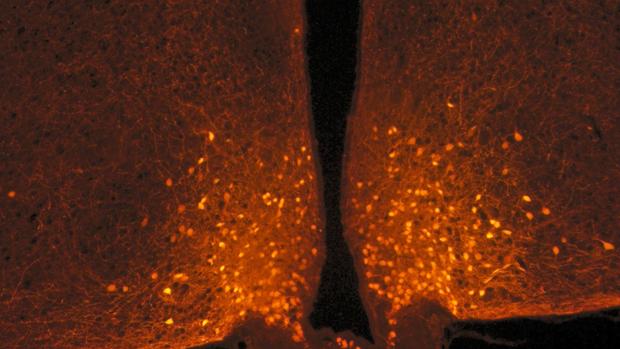

¿Por qué cuándo terminamos de comer nos sentimos llenos? La razón la acaban de descubrir investigadores franceses y reside en una serie de reacciones desencadenadas por un aumento en los niveles de glucosa en sangre. Este estudio, publicado en «Cell Reports», puede ser de gran utilidad para el tratamiento de las enfermedades relacionadas con los trastornos alimentarios y la obesidad. Los circuitos neuronales de nuestro cerebro que rigen los sentimientos de hambre y saciedad pueden modificar sus conexiones, ajustando así el comportamiento de alimentación a las condiciones de vida y manteniendo un equilibrio entre la ingesta de alimentos y el gasto calórico. Ahora, los científicos sospechan que esta plasticidad podría estar alterada para sujetos obesos. Ahora, los científicos sospechan que esta plasticidad podría estar alterada para sujetos obesos. En este nuevo estudio realizado en ratones, el equipo dirigido por Alexandre Benani, investigador del Centro Nacional para la Investigación Científica (CNRS), ha demostrado que estos circuitos se activan en la escala de tiempo de una comida, regulando posteriormente el comportamiento de alimentación. Sin embargo, esta activación no ocurre a través de un cambio en las «conexiones» del circuito. Los científicos se centraron en las neuronas POMC del hipotálamo, ubicadas en la base del cerebro, que son conocidas por limitar la ingesta de alimentos. Están conectadas a una gran cantidad de neuronas de otras áreas del cerebro, y las conexiones de este circuito son maleables: es decir, se pueden hacer y deshacer muy rápidamente en función de las fluctuaciones hormonales. Los investigadores observaron que este circuito neuronal no se modifica después de una comida equilibrada, sino que otras células nerviosas asociadas con las neuronas POMC, conocidas como astrocitos, en realidad cambian de forma. Después comer, los niveles de glucosa en sangre (glucemia) aumentan temporalmente, y los astrocitos detectan esta señal y se retraen en menos de una hora: una vez que se libera este «freno», se activan las neuronas POMC, lo que finalmente promueve la sensación de saciedad. Los astrocitos son células nerviosas en forma de estrella que se estudiaron por primera vez por su papel de apoyo con respecto a las neuronas. En condiciones habituales, envuelven a las neuronas POMC y actúan como frenos al limitar su actividad. Después comer, los niveles de glucosa en sangre (glucemia) aumentan temporalmente, y los astrocitos detectan esta señal y se retraen en menos de una hora: una vez que se libera este "freno", se activan las neuronas POMC, lo que finalmente promueve la sensación de saciedad. Sin embargo, sorprendentemente, una comida rica en grasas no conduce a esta remodelación. ¿Significa esto que los lípidos son menos efectivos para satisfacer el hambre? Los científicos están tratando de determinar si desencadenan la saciedad a través de otro circuito. También queda por determinar si los edulcorantes tienen los mismos efectos, o si atraen al cerebro al proporcionar una sensación adictiva de dulzura sin satisfacer el hambre.Fuente Salud https://ift.tt/38vV3Xa